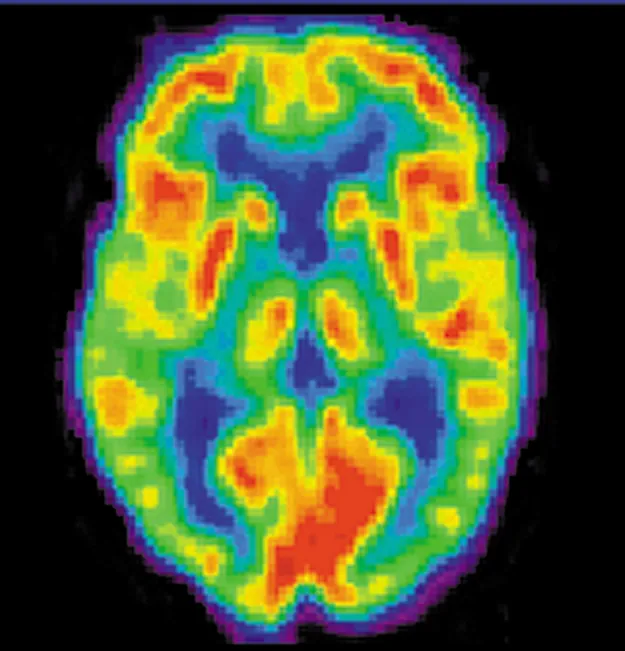

A brain scan. Different regions of the brain are shown in different colors.

Figure 32.4 A radiopharmaceutical is used to produce this brain image of a patient with Alzheimer’s disease. Certain features are computer enhanced. (credit: National Institutes of Health)